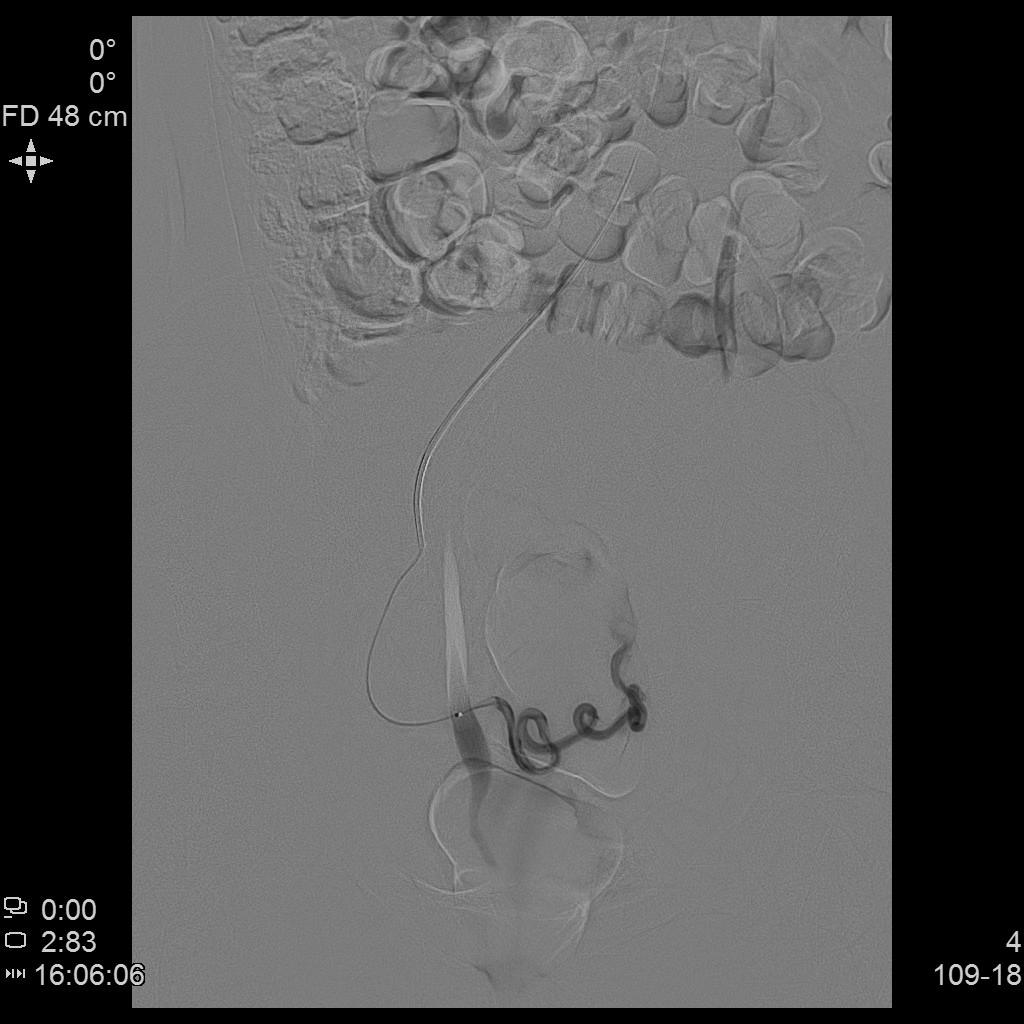

从手上扎针插管即可治肌瘤!——经桡动脉入路子宫动脉栓塞术

中年女性,发现子宫肌瘤进行性增大5年余。复查彩超提示多发肌瘤,较前明显增大(最大者直径近10cm)。近半年尿频、尿急症状进行性加重,考虑增大的子宫肌瘤压迫膀胱所致。

- MRI显示多发子巨大宫肌瘤,压迫膀胱。

- 经左侧桡动脉穿刺置入导管鞘,将导管送至双侧髂内动脉,再使用微导管超选择性插管至双侧子宫动脉主干远端。与传统股动脉入路进行手术疗效并无差异,仅是血管入路不同,其余手术操作相同,最终插管终点仍为子宫动脉主干远端。

- 术后桡动脉压迫止血8小时。